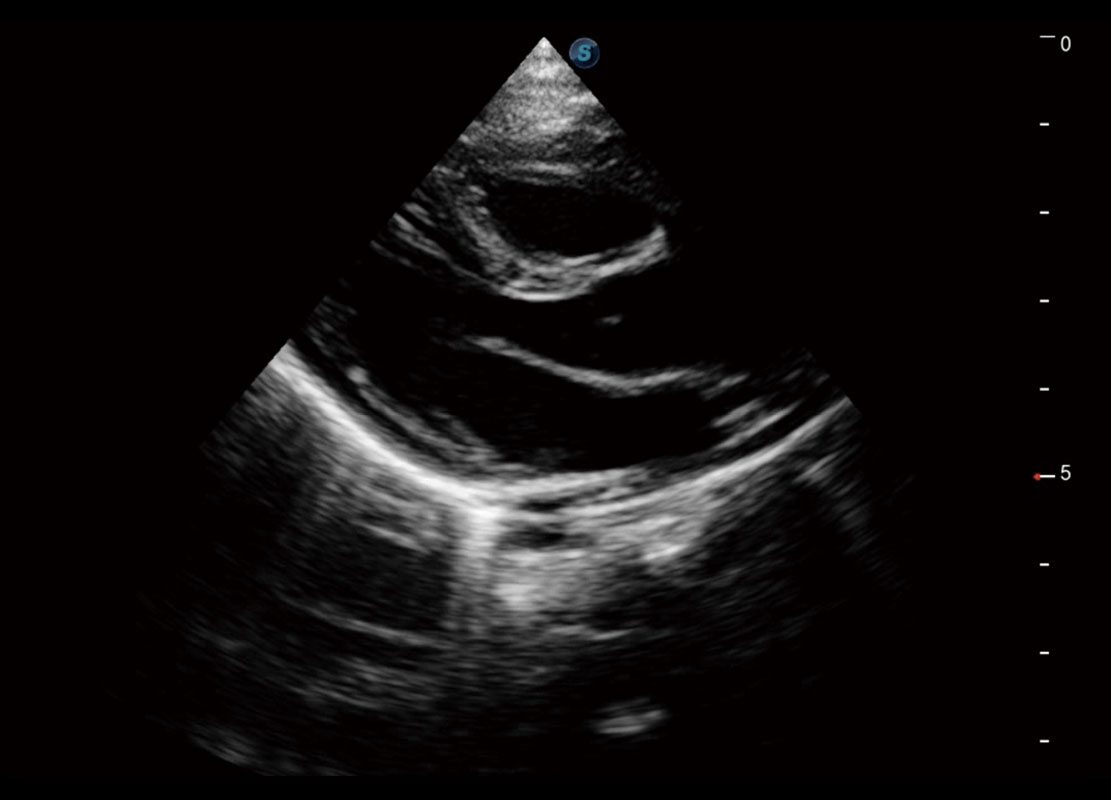

四腔切面

四腔心血流

P60搭载一系列胎儿心脏成像技术,实现精细的胎儿心脏评估。